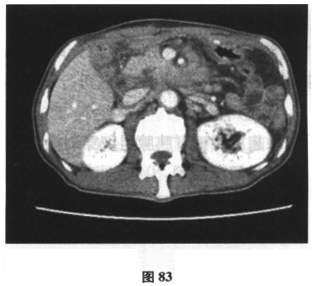

患者男,71岁,因“反复腹胀、纳差6个月,加重伴尿色加重1周余”入院。患者6月前开始肝中上腹胀,进食后加重伴纳差,就诊后予保护胃黏膜治疗症状无缓解。近一月来患者腹胀、纳差较前加重,门诊行胃镜及活检检查示慢性中度萎缩性胃炎伴肠化生,呼气试验示Hp(+),予三联方案(兰索拉唑、左氧氟沙星、克拉霉素)进行Hp根除治疗(该患者青霉素皮试+),停药4周后复查呼气试验示仍(+),调整抗生素后予四联疗法(奥美拉唑、左氧氟沙星、果胶铋、克拉霉素)继续根除治疗,但服药疗程未结束时患者腹胀、纳差加重,伴恶心、呕吐,尿色如浓茶样,伴皮肤黄染,于门诊查肝功能示总胆红素113.7μmol/L,结合胆红素64.5μmol/L,ALT110U/L,AST72U/L,尿常规:胆红素(++)。近2个月体重减轻7.5kg。患者既往于2年前有“肺大疱手术”史,有高血压史6月余,血压最高150/90mmHg,未规律服药。查体:神清,精神尚可,体型消瘦,皮肤巩膜明显黄染,未见肝掌、蜘蛛痣,腹软,无压痛,未及包块,双下肢无水肿。腹部B超未见异常。提示患者进一步检查示肝炎病毒指标、自身抗体均阴性。上腹部增强CT示:胆囊炎,肝内胆管稍扩张(图80),胰腺饱满(图81、图82),肠系膜、后腹膜淋巴结肿大(图83)。胸片显示患者肺部有术后金属物质。根据下面的检查提示,患者可能的诊断是什么?应进一步行何种检查()